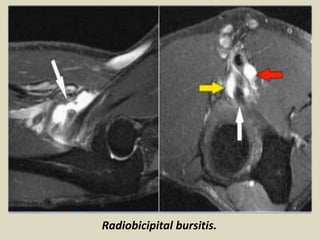

Bicipitoradial bursitis refers to inflammation of the bicipitoradial bursa.

The bicipitoradial bursa surrounds the biceps tendon in supination. In pronation, the radial

Radiobicipital bursitis.

Bicipitoradial bursitis: axial T1, T2-weighted image showing a isointense

enlarged bicipitoradial bursa. Green arrow: biceps tendon.

Bicipitoradial bursitis secondary to a nodular fasciitis: axial STIR & T1-weighted fat saturated

contrast-enhanced sequence demonstrating the biceps tendon and the bicipitoradial bursa

compressed by a homogeneous moderately hyperintense mass showing no significant enhancement.

Green arrow: tissular mass. Red arrow: biceps tendon. Yellow arrow: bicipitoradial bursitis